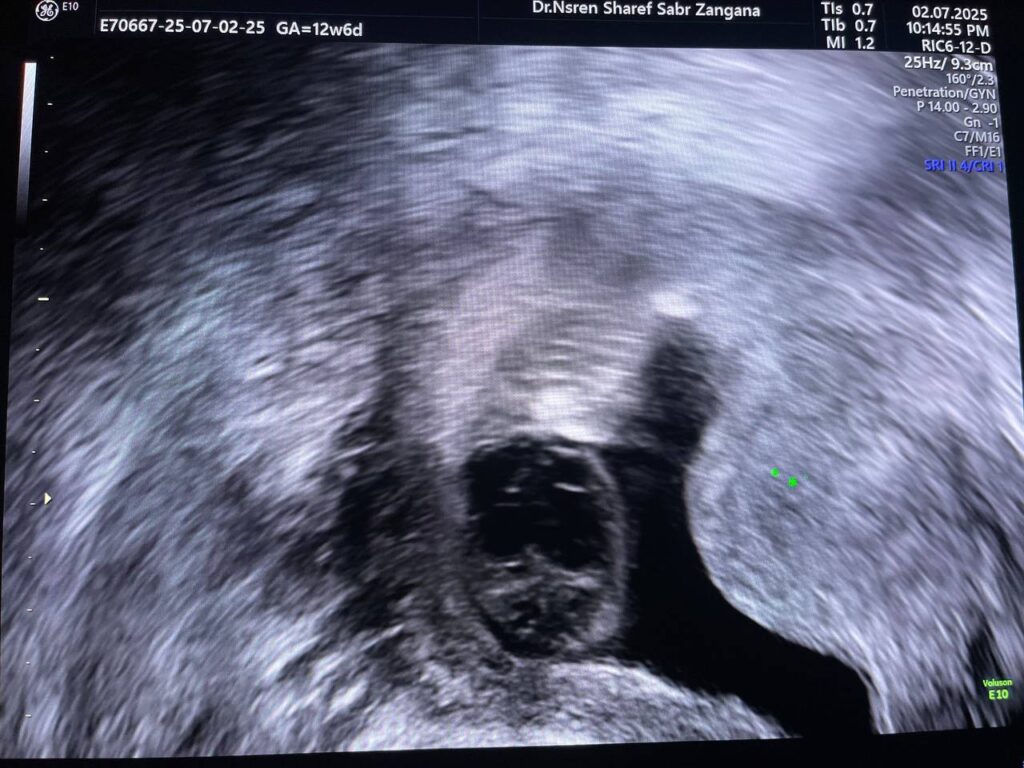

Increase nuchal translucency 7.3mm , mild diffuse skin edema ,Hypoplastic nasal bone, congenital heart disease can not be excluded , please for chromosomal study